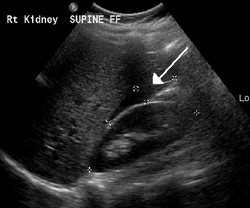

A small amount of anechogenic-free fluid in the recto-uterine pouch is commonly found in both intrauterine and ectopic pregnancies.[5] The presence of echogenic fluid is estimated at between 28 and 56% of women with an ectopic pregnancy, and strongly indicates the presence of hemoperitoneum.[5] However, it does not necessarily result from tubal rupture but is commonly a result from leakage from the distal tubal opening.[5] As a rule of thumb, the finding of free fluid is significant if it reaches the fundus or is present in the vesico-uterine pouch.[5] A further marker of serious intra-abdominal bleeding is the presence of fluid in the hepatorenal recess of the subhepatic space.[5]